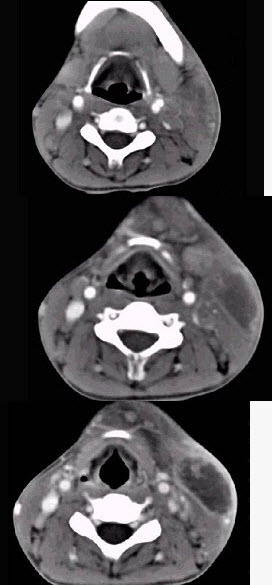

男性,67岁,颈部出现疼痛性肿块半年余,CT扫描如图所示,最可能的诊断是()。

A、神经鞘瘤

B、囊肿

C、淋巴结核

D、淋巴瘤

E、血管瘤

D